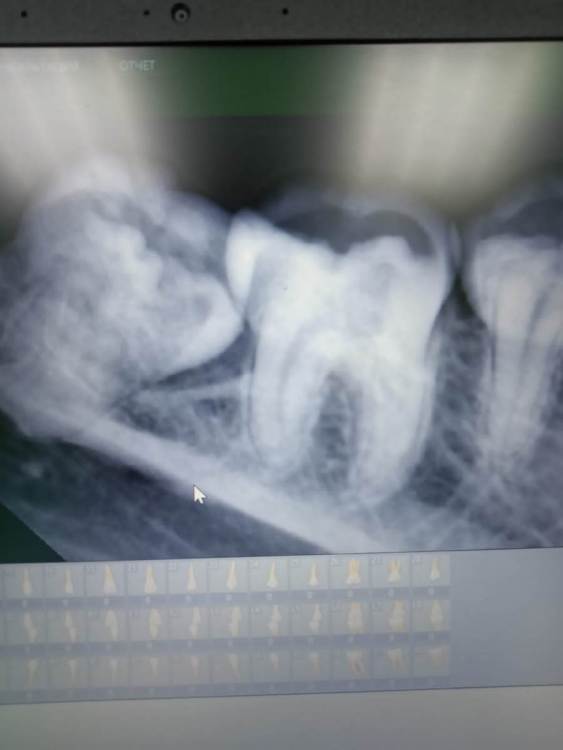

Кариес Опубликовано 19 апреля, 2022 Поделиться Опубликовано 19 апреля, 2022 Здравствуйте! У меня такая проблема. 8ка нижняя справа. Снимок во вложении. Зуб ретинированный и лезет вбок так как не хватает пространства в челюсти. Пока здоровый что видно на снимке, но так как уровень зубов разный то есть вероятность развития кариеса на 8 и даже на 7 зубе. Есть радикальный метод это удаление 8го зуба но к нему прибегать не хотелось бы. Подскажите пожалуйста есть ли возможность избежать возникновение кариеса и удаления зуба, возможно как нибудь нарастить 8зуб, что бы они были на одном уровне с 7мым и туда не забивались остатки пищи. Хотелось бы противодействовать развитию кариеса на ранней стадии. Ссылка на комментарий

Женька Опубликовано 19 апреля, 2022 Поделиться Опубликовано 19 апреля, 2022 (изменено) 4 минуты назад, Кариес сказал: Хотелось бы противодействовать развитию кариеса на ранней стадии. Здравствуйте. Хотите противодействовать и сохранить (сохранить, я повторю) седьмой зуб - удаляйте дистопированный 8. Как бы Вам не хотелось, но это решение, которое решит Вашу проблему. Изменено 19 апреля, 2022 пользователем Женька 1 4 Ссылка на комментарий